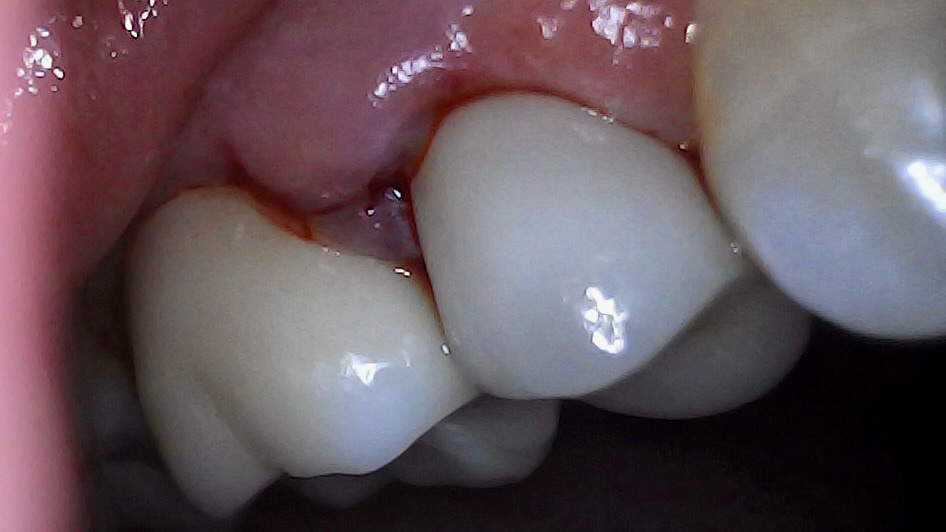

Palatal margin